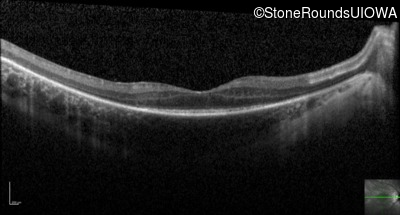

Optical Coherence Tomography - Right - 20/60

Exemplar / OCT Stack